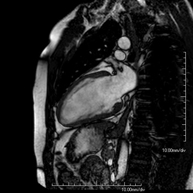

This non-invasive diagnostic test yields morphological and functional information about the heart and adjacent structures. In this way, different congenital and acquired pathologies can be diagnosed, or checks can be carried out on patients with previously known pathologies. In the vast majority of cases, intravenous contrast (gadolinium) is required to complete the study. This type of contrast rarely causes adverse reactions. During the test, the technician will ask the patient to hold their breath several times for 10–15 seconds to obtain the clearest images possible. No prior preparation is required by the patient. The test lasts approximately 45–60 minutes. It is not recommended for patients with pacemakers. Patients should nevertheless inform the doctor if they have metal implants and/or surgical clips.